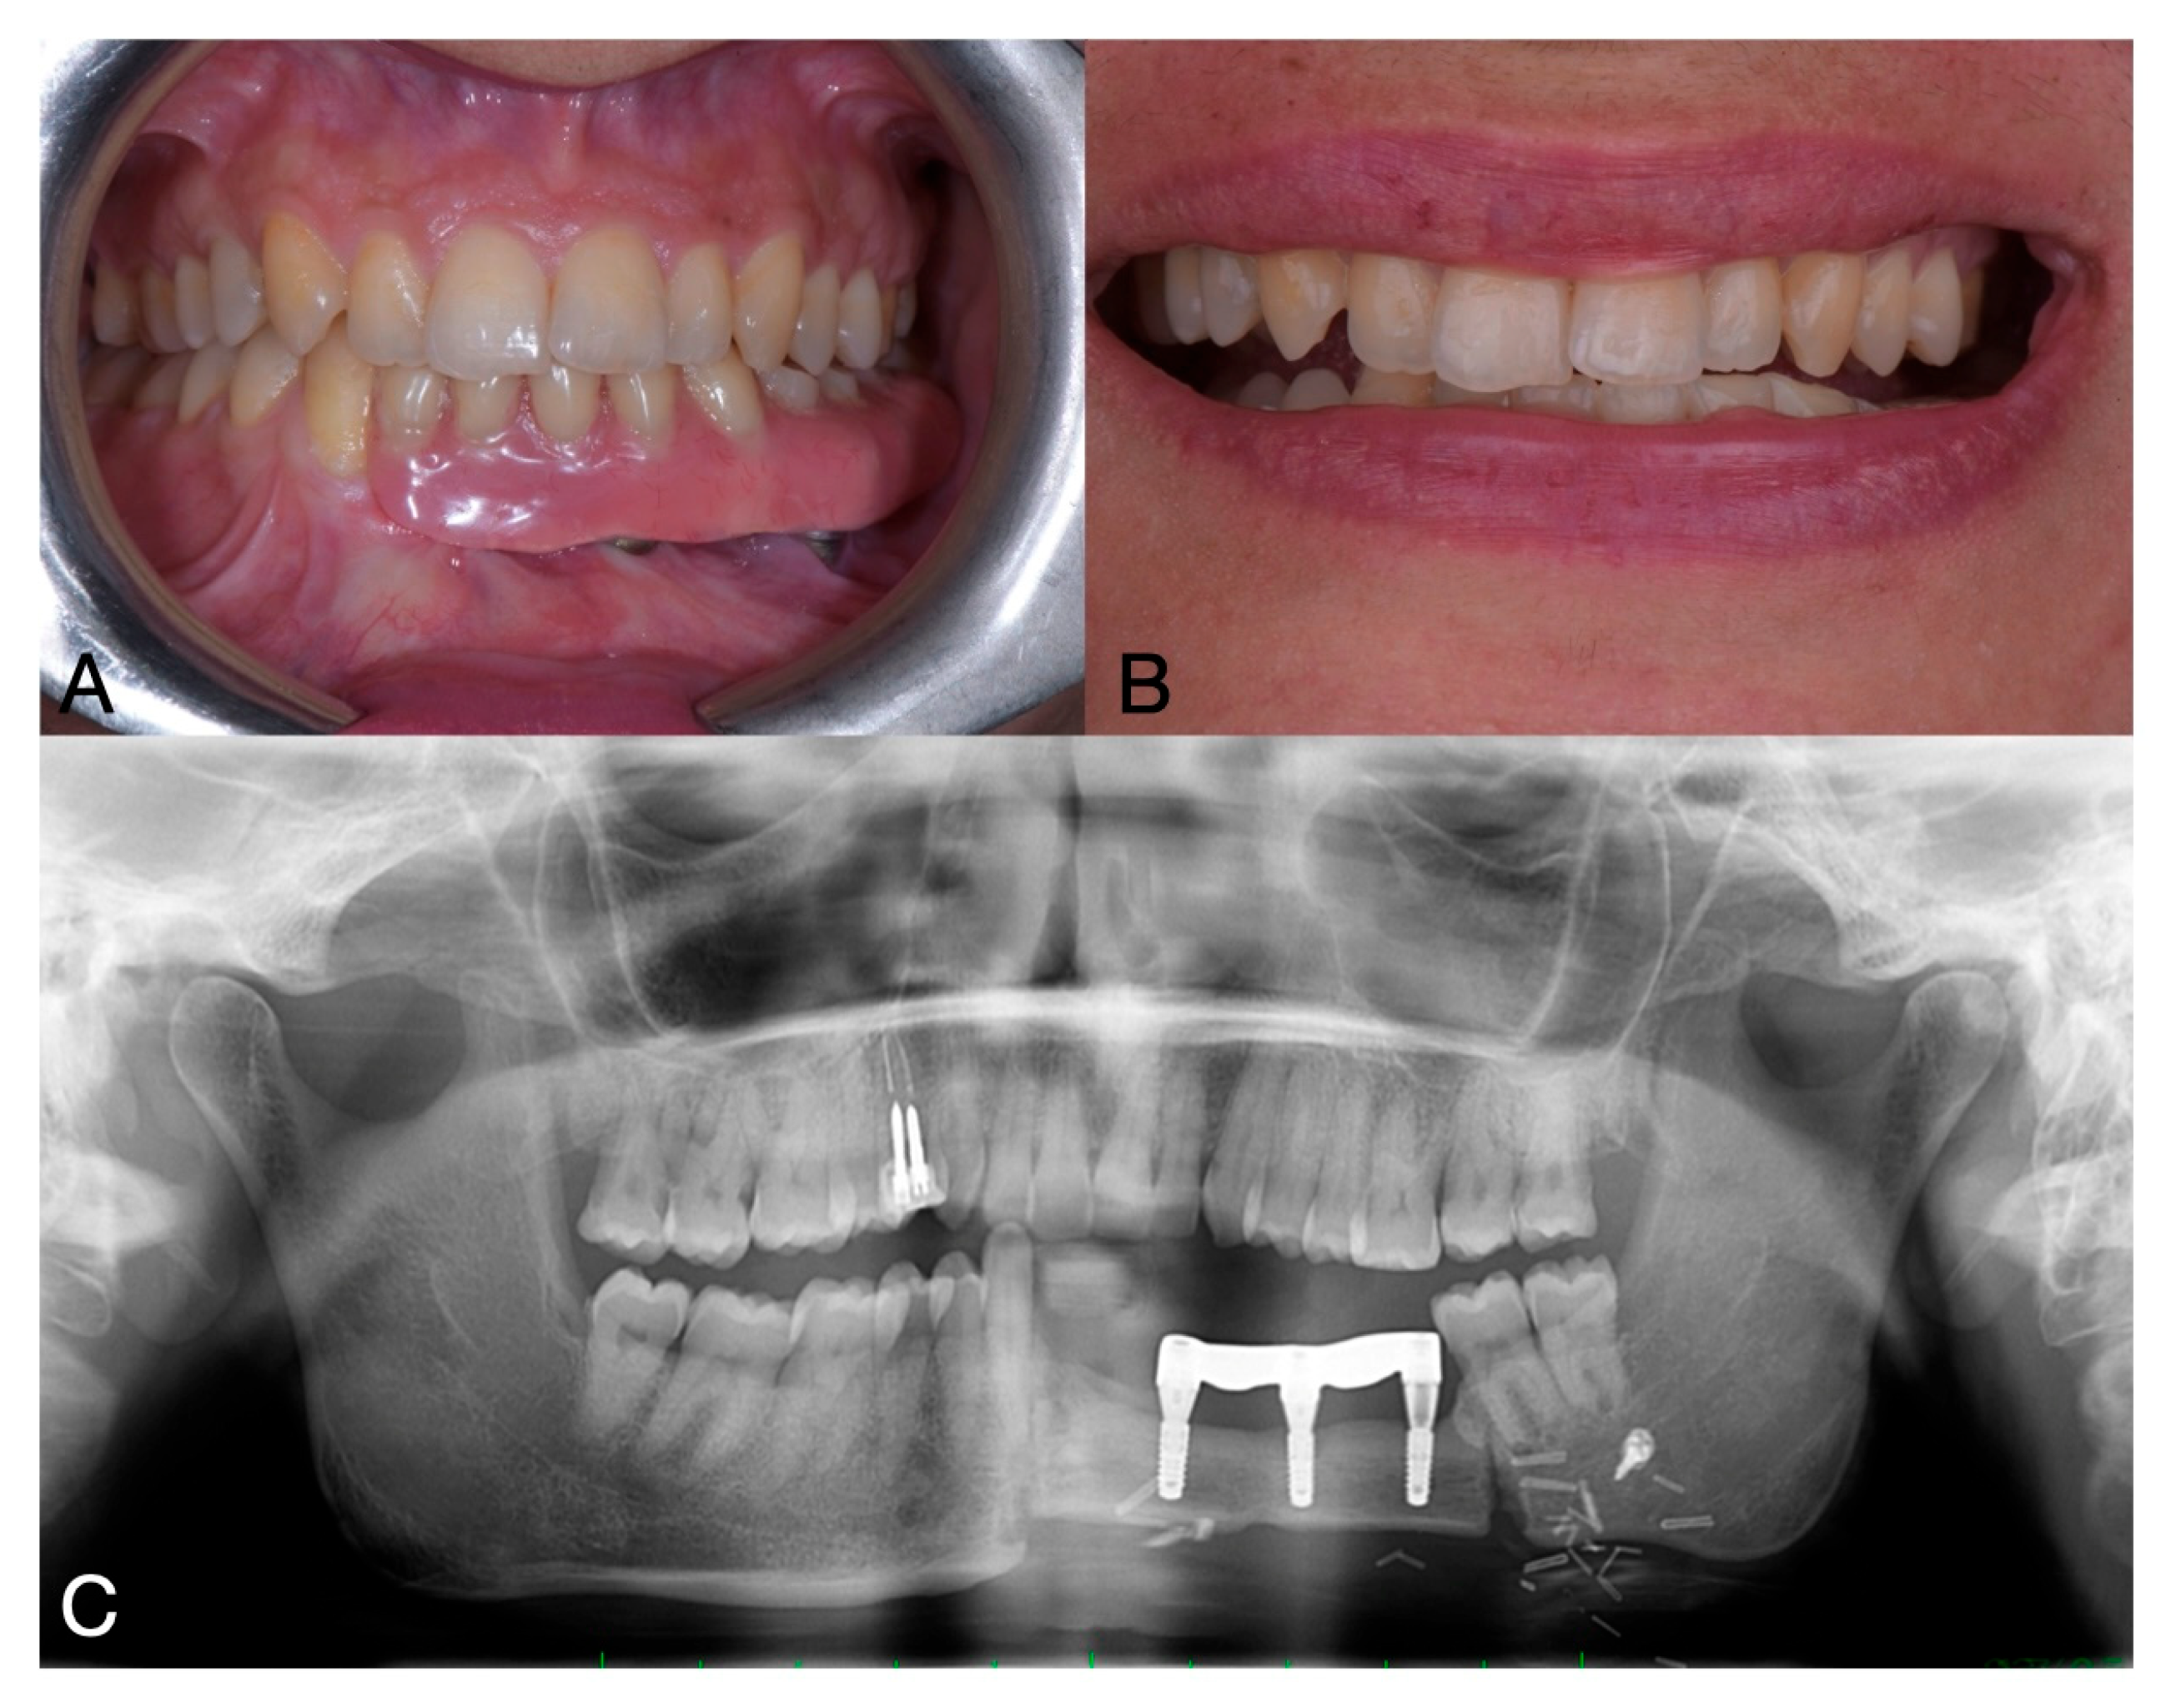

One year after the mandibular surgery, on OPG was performed to plan the subsequent implant-prosthetic rehabilitation (Figure 5).

Figure 5.

Pre-operative clinical situation (A,B) and OPG (C).

Analogic impressions were taken with the use of polyether impression material. Performing this prosthetic rehabilitation was challenging because taking impressions on the implants was difficult due to the patient’s limited mouth opening, as the muscles had been cut during the reconstructive surgery of the mandible. With the prosthesis, restoration of masticatory function and improvement in facial aesthetics were observed. The patient experienced a positive impact on her self-esteem and social interactions (Figure 7).

Figure 7.

Clinical (A,B) and radiographic (C) situation after prosthetic delivery.

Patient satisfaction was evaluated using a Visual Analogue Scale (VAS) ranging from 0 to 10, assessing both aesthetic and functional outcomes. The patient reported the highest possible score—10 in both categories—indicating maximum satisfaction. Overall, the patient expressed a high level of satisfaction with the treatment outcomes.